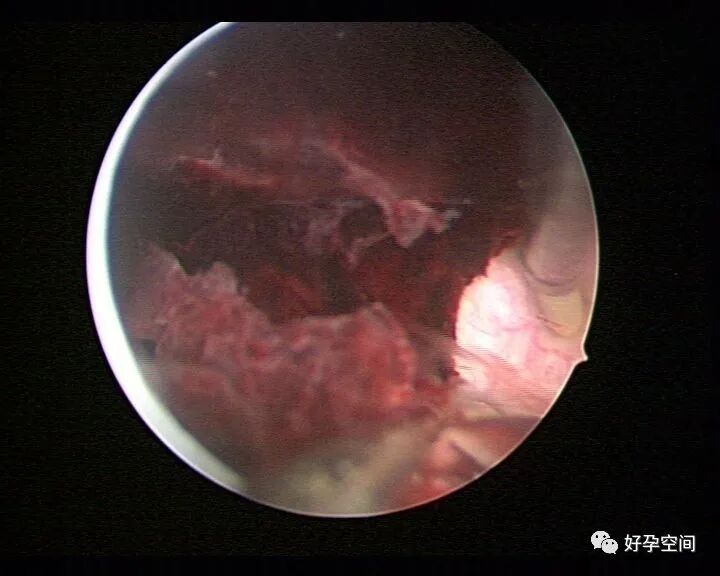

病例3:(病人年龄及取卵个数不详)取卵术后血尿膀胱内血块尿潴留,膀胱灌洗效果不佳,宫腔镜探查膀胱,清除血块,膀胱多处穿刺伤,电凝止血。

病例4:32岁,取卵13枚,取卵术后血尿膀胱内血块尿潴留,膀胱灌洗效果不佳,宫腔镜探查膀胱,清除血块,膀胱底见穿刺伤,电凝止血。